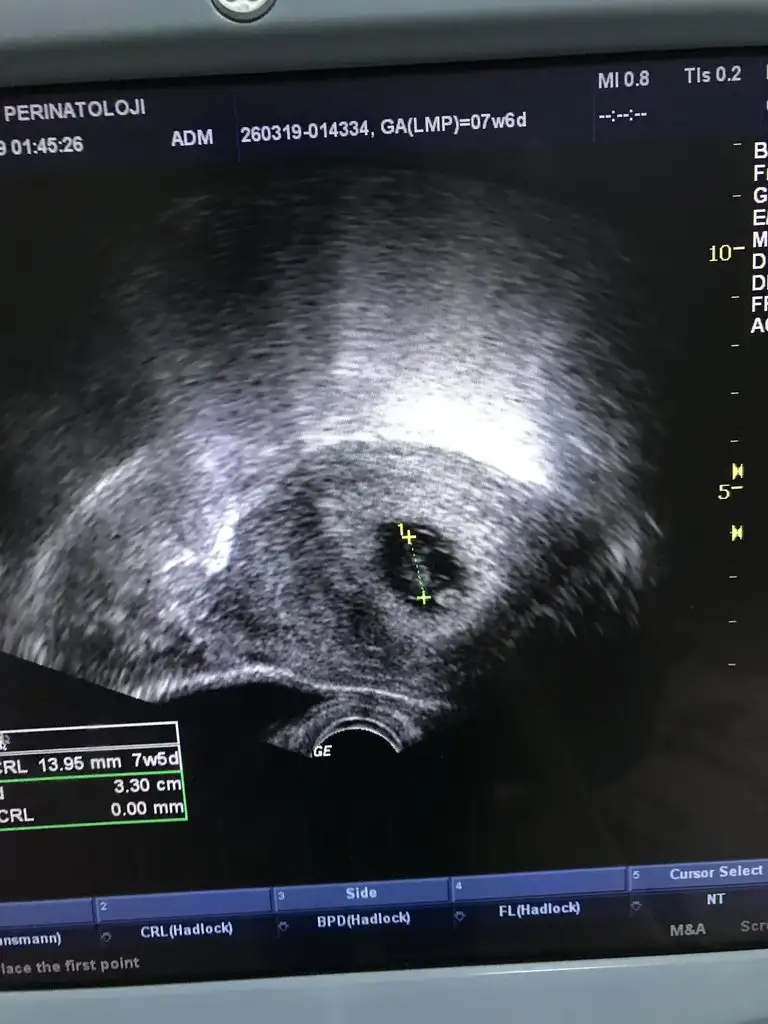

9+0 olmamız gerek ama ultrasonda 9+6 çıktık :) cinsiyet tahmini nedir? :)))